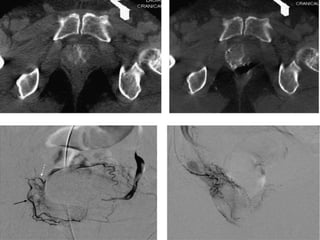

The prostate gland is a pyramid-shaped organ that weighs approximately 20 grams and measures 3x4x2 cm. It has three zones - the peripheral zone (70%), central zone (25%), and transitional zone (5-10%). Prostate cancer develops in the peripheral zone, while benign prostatic hyperplasia (BPH) develops in the transitional zone. The prostate receives its blood supply from various arteries, most commonly the internal pudendal artery (34%). Knowing the detailed arterial anatomy is important for procedures like prostate artery embolization (PAE) to treat conditions like BPH and prostate cancer. Imaging tools like CT angiography and cone beam CT can help the interventional radiologist map the arterial supply before